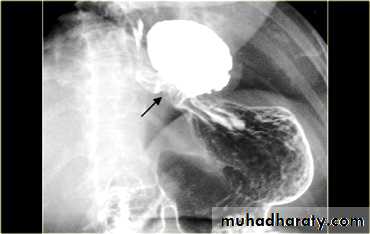

LEFT: Dilated esophagus (arrows) appears as long, well-defined structure paralleling heart RIGHT: Dilated esophagus usually deviates to right. Narrowing (arrow) at hiatus.

GIT

LEFT: CT shows dilated esophagus (arrow) that led to esophagram.RIGHT: Esophagram shows narrowing (arrow) at level of hiatus.